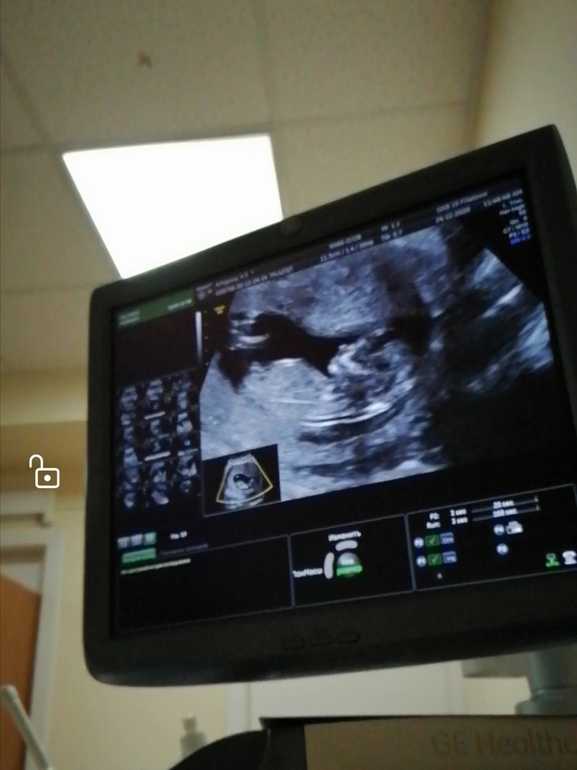

А это скрины с узи моего сладкого Сыночка👶💙💙💙🙏🙏🙏

Тут писюльку видно вид снизу. Писюльку между ножек